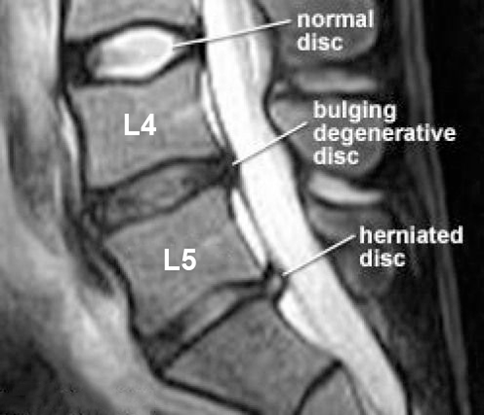

Lumbar lifting injury can cause _____

herniation

Grandparent picking up grandchild and hears a pop and feels the pain

Could be lumbar herniation

In Lumbar L4/L5 intervertebral disk herniate laterally pinch ___, herniate medially (paracentral) pinch __

L4 (match)

L5

Lumbar vs cervical spine herniation

What nerve would L4-L5 intervertebral lateral herniated disk compress?

L4 (medial would be L5)